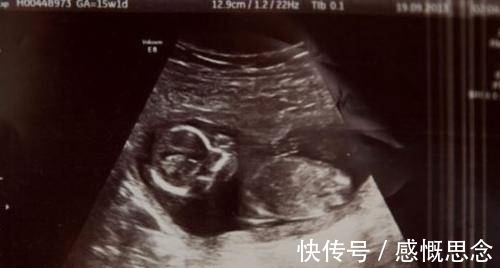

家住爱尔兰基尔代尔的女子米歇尔(Michelle Hui)在怀孕6个月时出现出血症状,去医院拍了五份扫描片,以防感染,医生建议她进行人工流产,采用药物堕胎的方式打掉孩子。

进行过药物堕胎后,她被检查出子宫内还含有血凝块,所以不得不进行手术移除。就在手术前,医生在她腹部检测到了心跳。医生告诉米歇尔,本来她怀的是双胞胎,其中的一个宝宝没能存活,而另一个则奇迹的存活了下来。